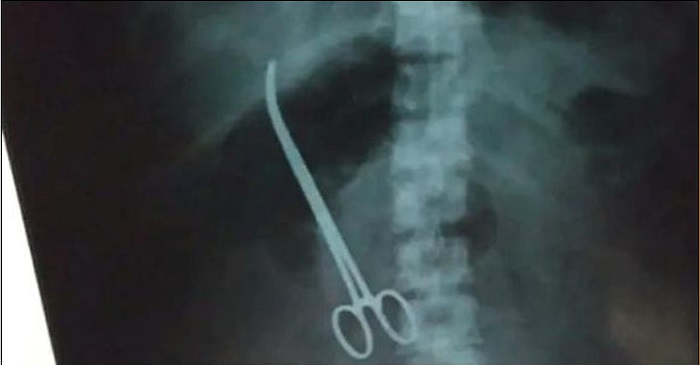

পেটের ভেতর কাঁচি রেখেই সেলাই দিলেন চিকিৎসক!

হায়দ্রাবাদের বিখ্যাত নিজাম ইনস্টিটিউট অব মেডিকেলে তিন মাস আগে অস্ত্রোপচারের জন্য ভর্তি হন ৩৩ বছর বয়সী এক নারী। হাসপাতালের চিকিৎসা শেষে বাড়িতে ফেরার পর থেকেই তিনি পেটের মারাত্নক যন্ত্রণায় ভুগতে থাকেন। মাস খানেক পর এক্স-রে করতেই বেরিয়ে এল অবহেলার এই নজির।

পরীক্ষা করতে তাকে ওই হাসপাতালেই নিয়ে এক্স-রে করানো হয়। এক্স-রে রিপোর্ট দেখেই চক্ষু চড়কগাছ তাঁর আত্মীয় এবং চিকিৎসকদের। রিপোর্টে দেখা যায় মহিলায় পেটের ভেতর রয়ে গেছে ছয় ইঞ্চি ডাক্তারি কাঁচি।

রোববার (১০ ফেব্রুয়ারি) সকালেই ফের অস্ত্রোপচার করে ওই যন্ত্রটি বের করা হয়। এনআইএমএসের পরিচালক কে মনোহর জানান, ‘রোগী আমাদের প্রথম অগ্রাধিকার। যত তাড়াতাড়ি সম্ভব আমরা রোগীর স্বাস্থ্য সমস্যা মিটিয়ে দিতে ওই উপকরণটি বের করে দিচ্ছি।’